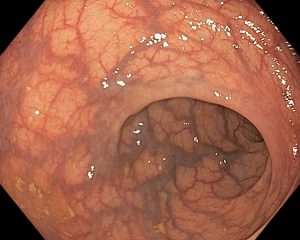

Атлас

В эндоскопическом атласе обычно представлены изображения и видео, полученные во время процедур, проводимых врачами-эндоскопистами. Эти изображения и видео могут использоваться для обучения студентов медицинских учебных заведений, повышения квалификации медицинских работников, а также для консультации врачей при диагностике и лечении различных заболеваний.